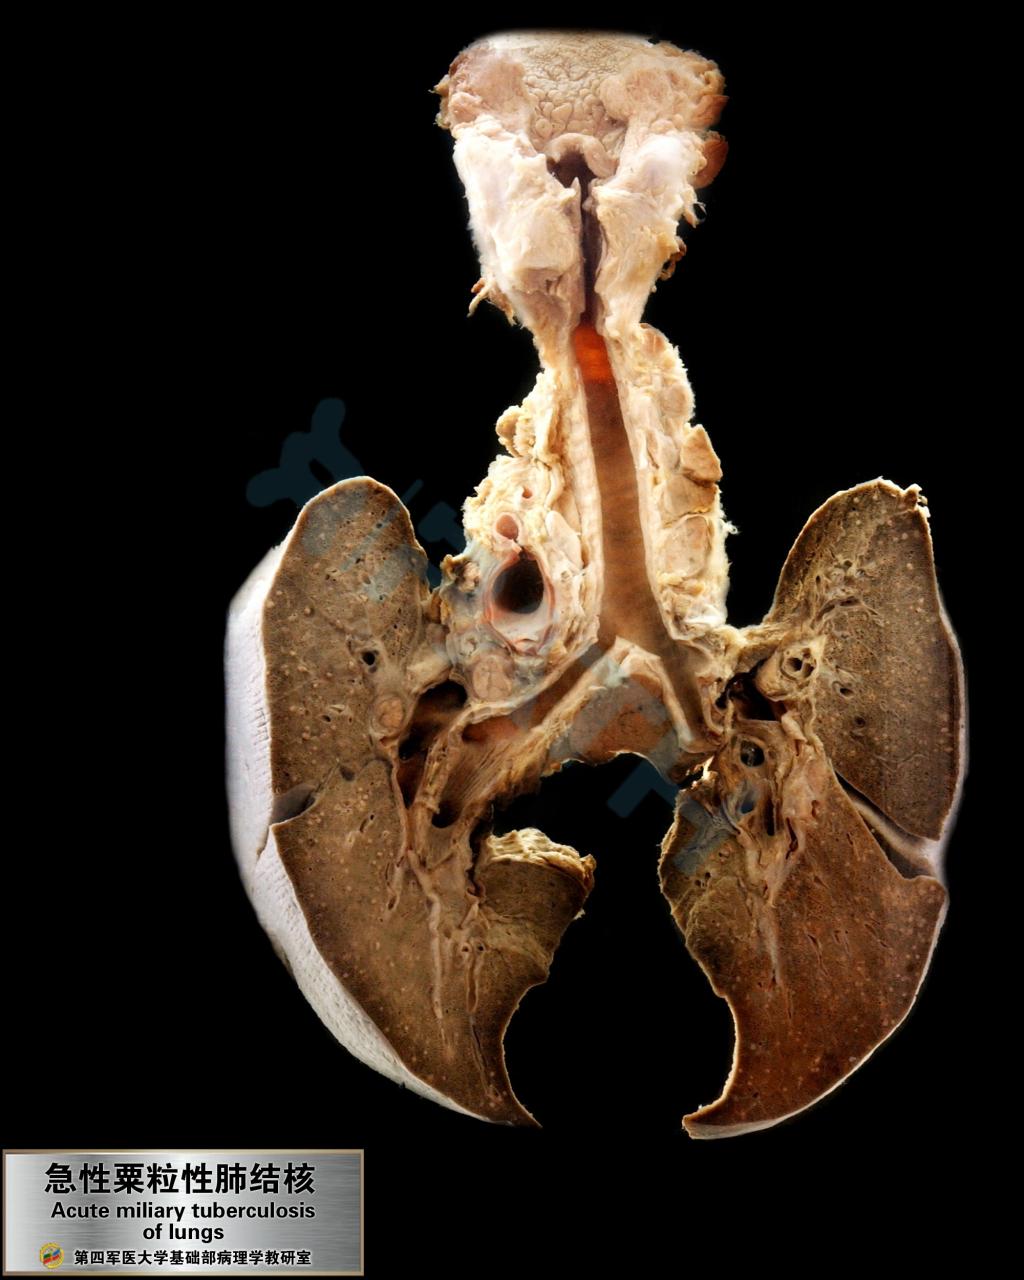

急性粟粒性肺结核

粟粒性肺结核